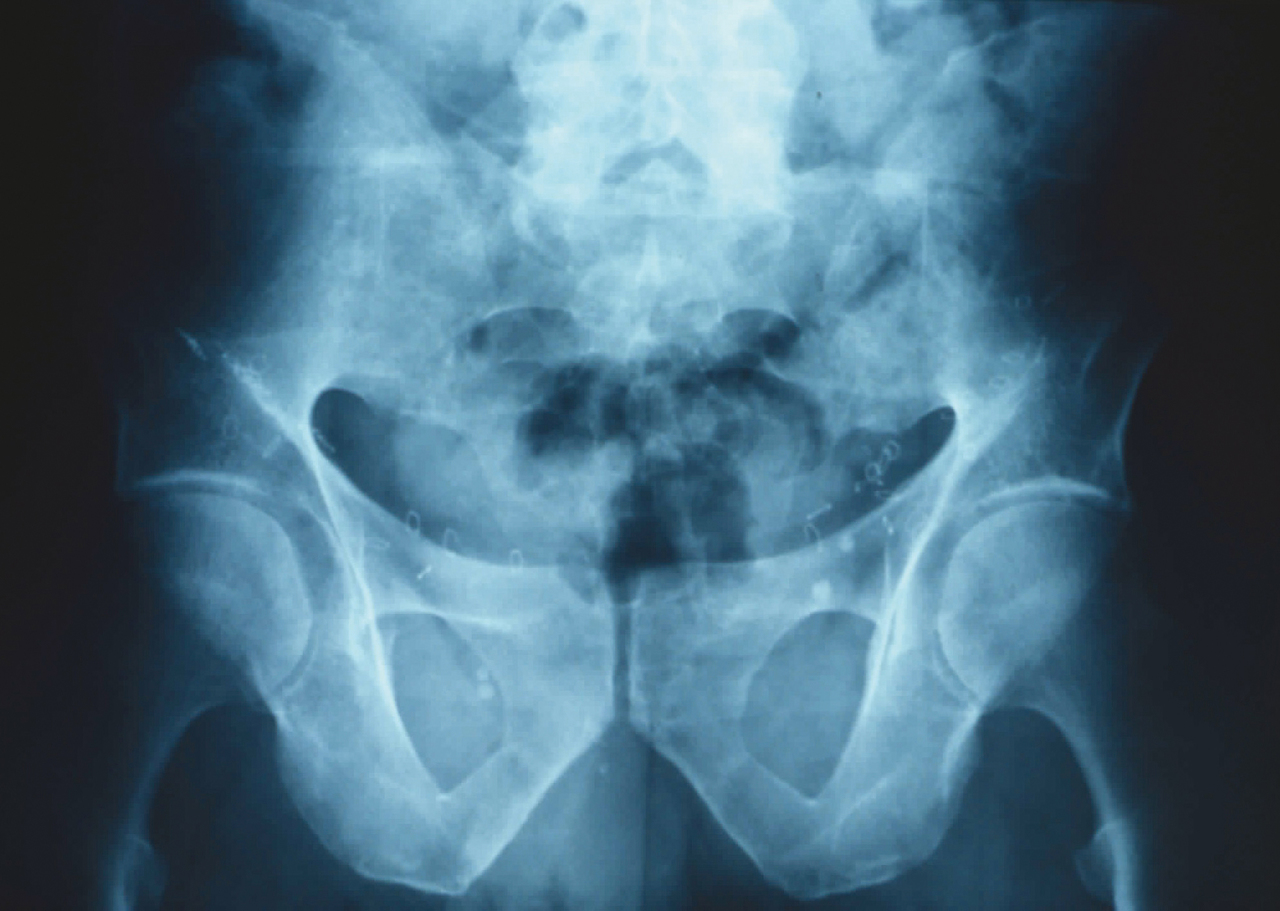

Quel est votre diagnostic ?

Il s'agit d'une sacro-iliite bilatérale.